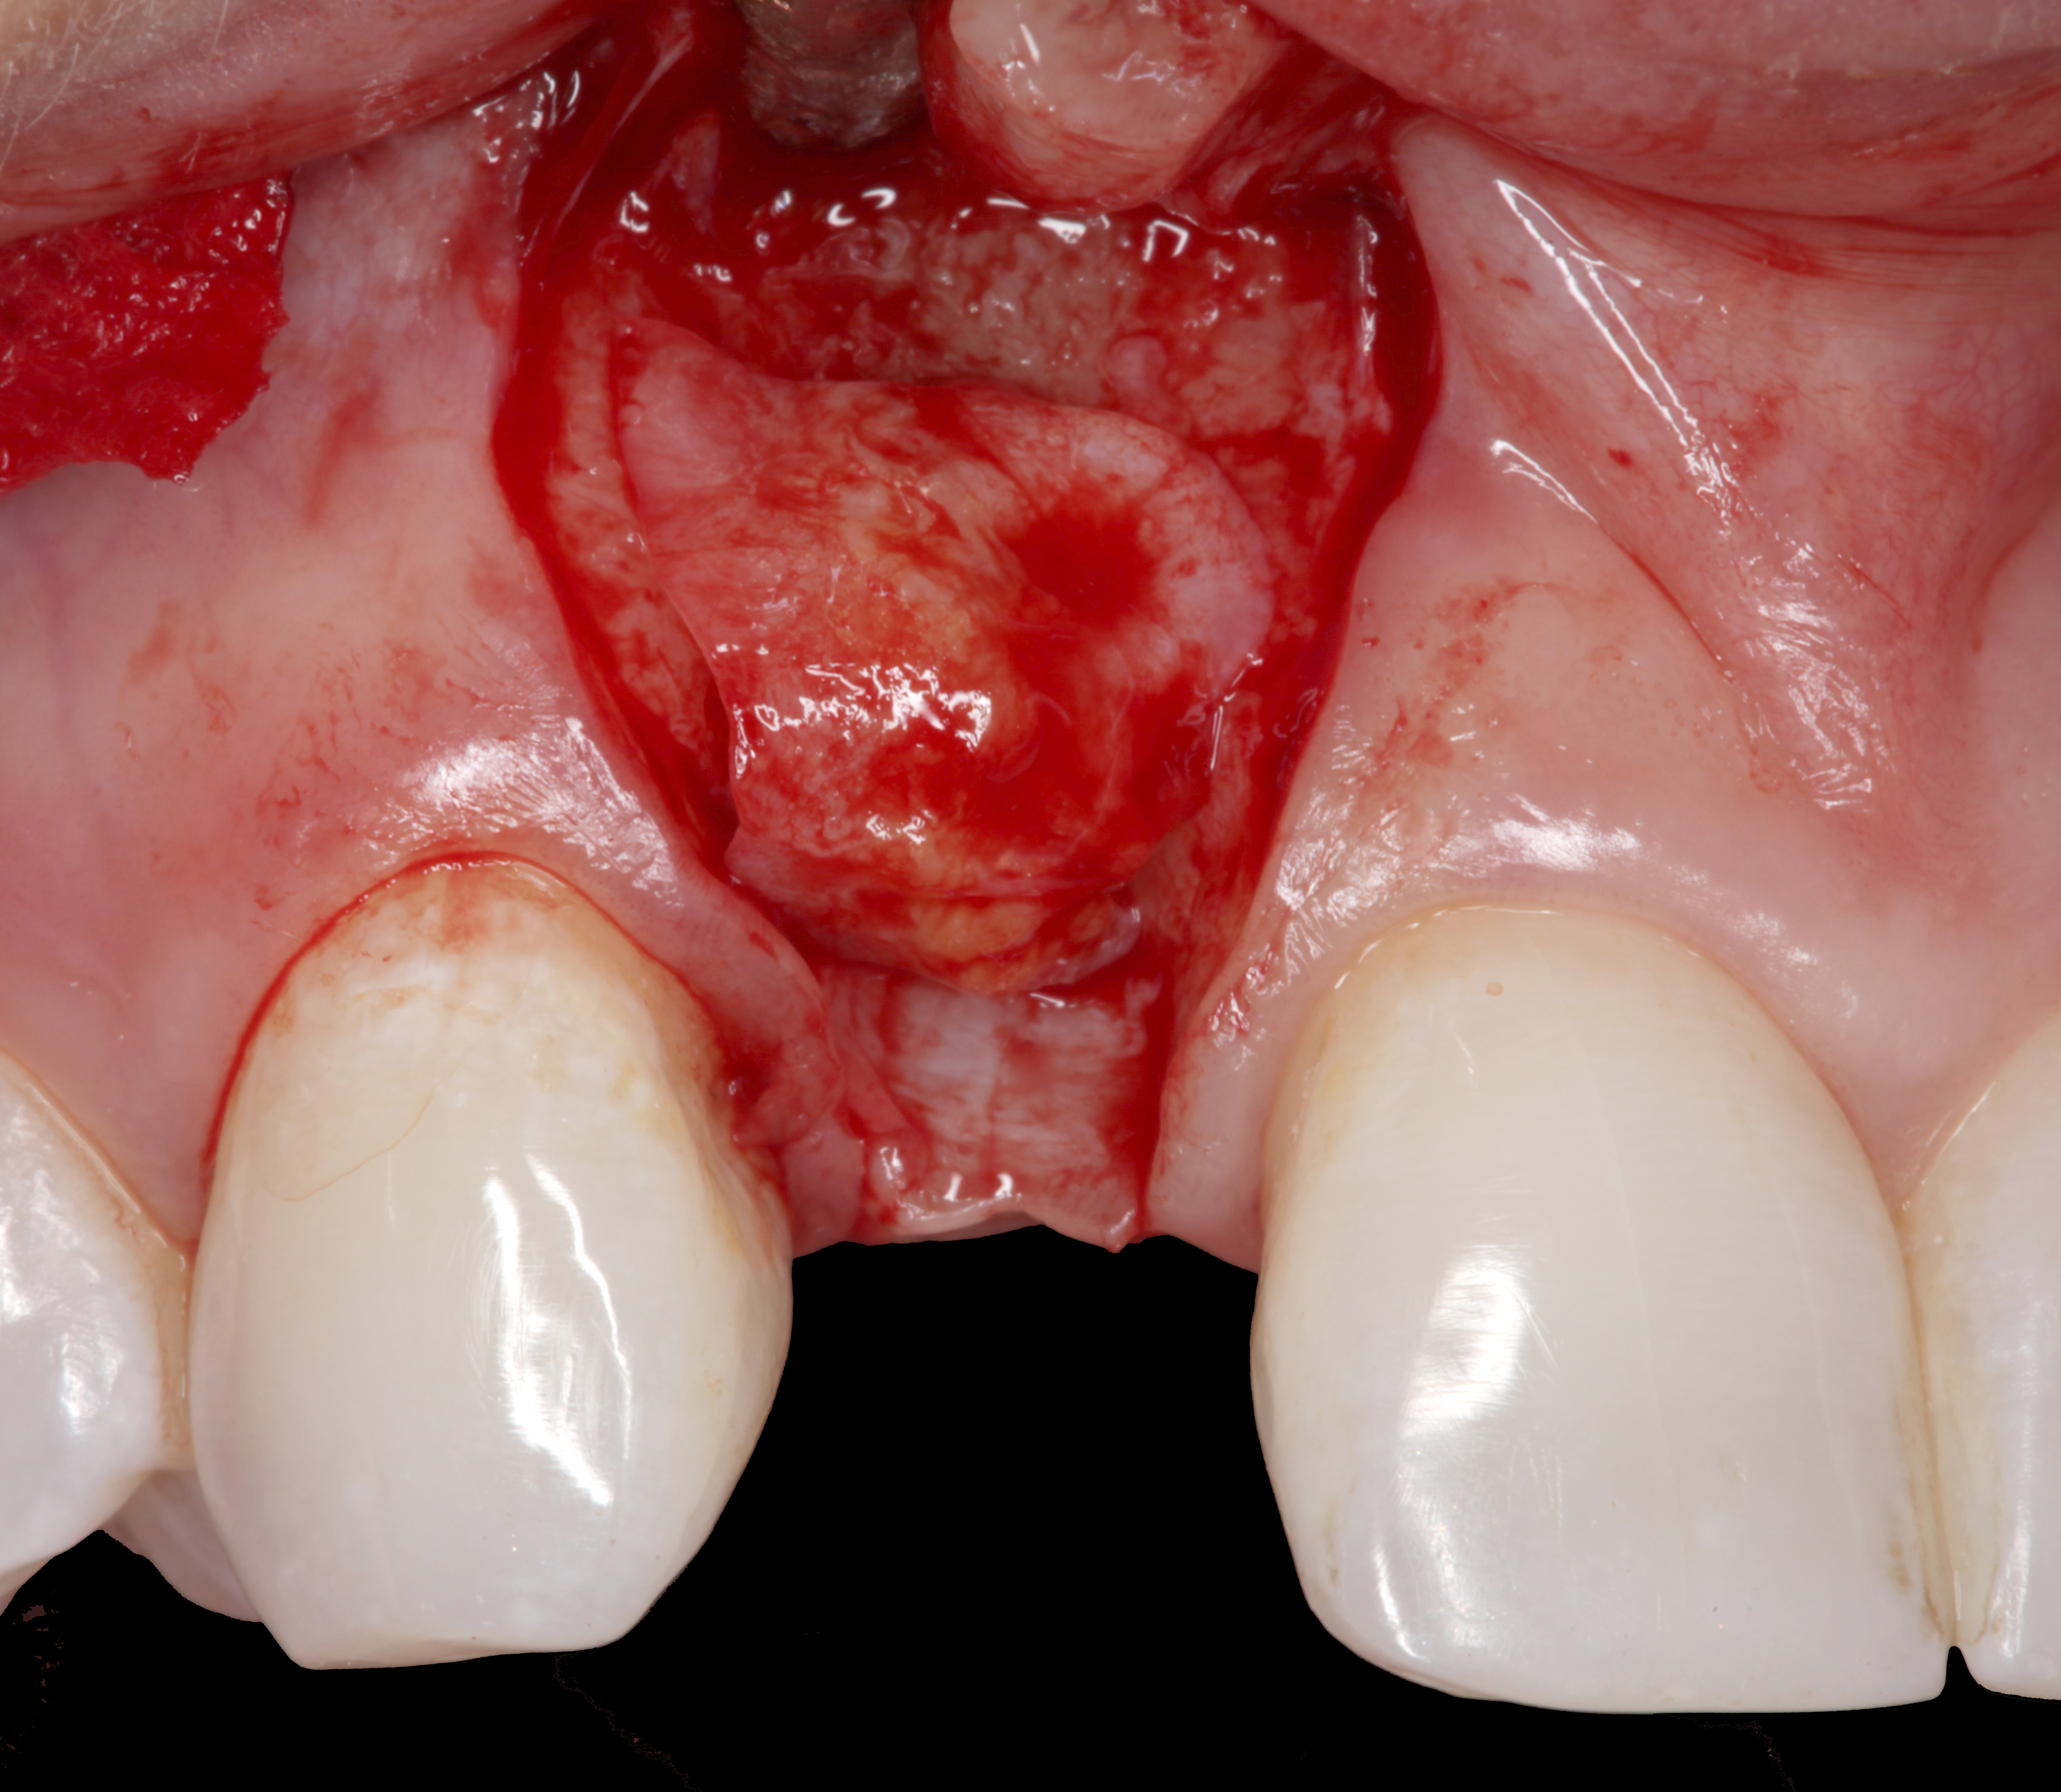

Fig 18. A full-thickness flap from teeth Nos. 18 to 20 revealed granulomatous tissue in the circumferential defect around implant No. 19.

Figure 18

Fig 19. The circumferential defect was debrided. Note excess cement extending apically from the margin of the crown into the defect; residual cement has been shown to be complicit in the development of peri-implant disease.

Figure 19

A surgical flap procedure was performed with the intent of thoroughly debriding the granulomatous tissue from the osseous defect (Figure 18 and Figure 19), mechanically and chemically detoxifying the surface of the implant (Figure 20 through Figure 22), and grafting the infrabony component of lesion with bone xenograft (Bio-Oss®, Geistlich Pharma, www.geistlich-na.com) in an attempt to reduce the vertical defect (Figure 23). To concurrently resolve the mucogingival problem, the plan called for placing a dermal allograft (Dermis Allograft, DENTSPLY International, www.dentsply.com) on the buccal (Figure 24) and then replacing the flap (Figure 25).